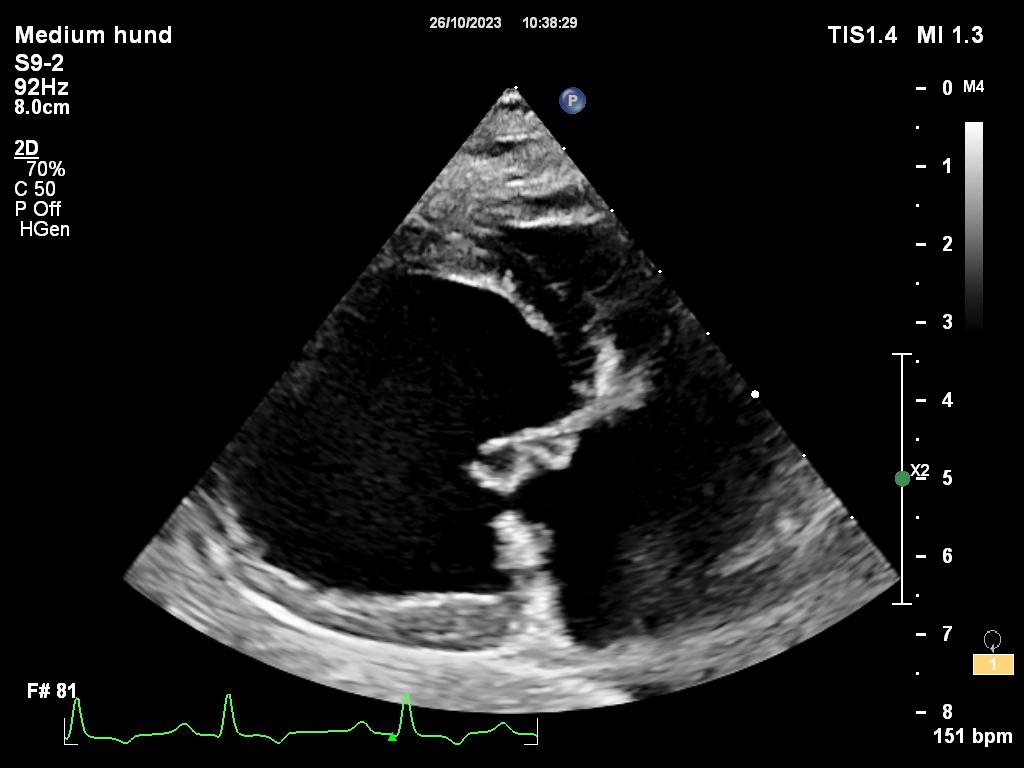

Sykdommen er genetisk betinget, oppstår i voksen alder og er oftest sett hos raser som Cavalier King Charles Spaniel, dachs og chihuahua. Klaffesykdom påvises oftest på mitralklaffen, som er klaffen som sitter mellom venstre forkammer og venstre hovedkammer. Hos hunder med MMVD vil mitralklaffen fortykkes slik at den ikke lukker seg helt igjen når blodet skal pumpes ut fra hovedkammeret gjennom aorta (hovedpulsåren). Dette fører til at noe av blodet strømmer tilbake til forkammeret og med tiden vil de venstre hjertekamrene forstørres. Disse hundene har en tydelig bilyd på hjertet og det anbefales en ultralydundersøkelse av hjertet for å avgjøre alvorlighetsgraden av sykdommen.

En ultralydundersøkelse av hjertet forteller om hunden din har utviklet forstørret forkammer og hovedkammer som følge av klaffesykdom. De hundene der hjertet har endret seg på grunn av klaffesykdommen har fordel av medisinsk behandling i form av tabletter som gis to ganger daglig. Dette er medisiner som hjelper hjertekamrene å trekke seg sammen. Medisinene forhindrer rask videreutvikling av sykdommen og senker risiko for utvikling av hjertesvikt. Hunder som får hjertemedisiner skal stå på disse livet ut, og det er sjelden man ser bivirkninger av denne typen tabletter.